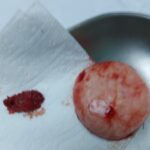

Jete gjati nuk behet jete shkurter (Ndjese per fotot)

Qeni ne foto erdhi ne klinike i mbajtur ne krahe sepse nuk ecte dot vete. I pa fuqishem edhe per te ngrene, shume i dobesuar. Sorrollatur mbi nje muaj e gjysem neper spitale e klinika veterinare i ” diagnostikuar ” prej tyre me semundje nga me te ndryshmet i mjekuar me lloje te ndryshme ilacesh por gjendja vazhdonte te rendohej.

Pas nje kontrolli te kujdesshem dhe analizave te kryera ne klinike nga ana jone u diagnostikua me tumor ne shpretke. U krye nderhyrje kirurgjikale dhe u gjet nje tumor me peshe 1,5 kg.

Pas rehabilitimit post operator ai tashme ka filluar te eci vete, te ushqehet vete dhe te filloje te luaj.

Ju kerkojme ndjese per fotot e tumorit por i botojme per ata profesioniste qe jane vertet te interesuar ne profesionin e tyre.